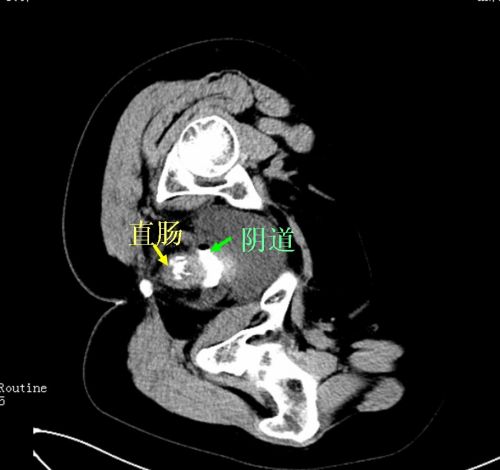

直肠阴道内均有造影剂,提示直肠阴道瘘。